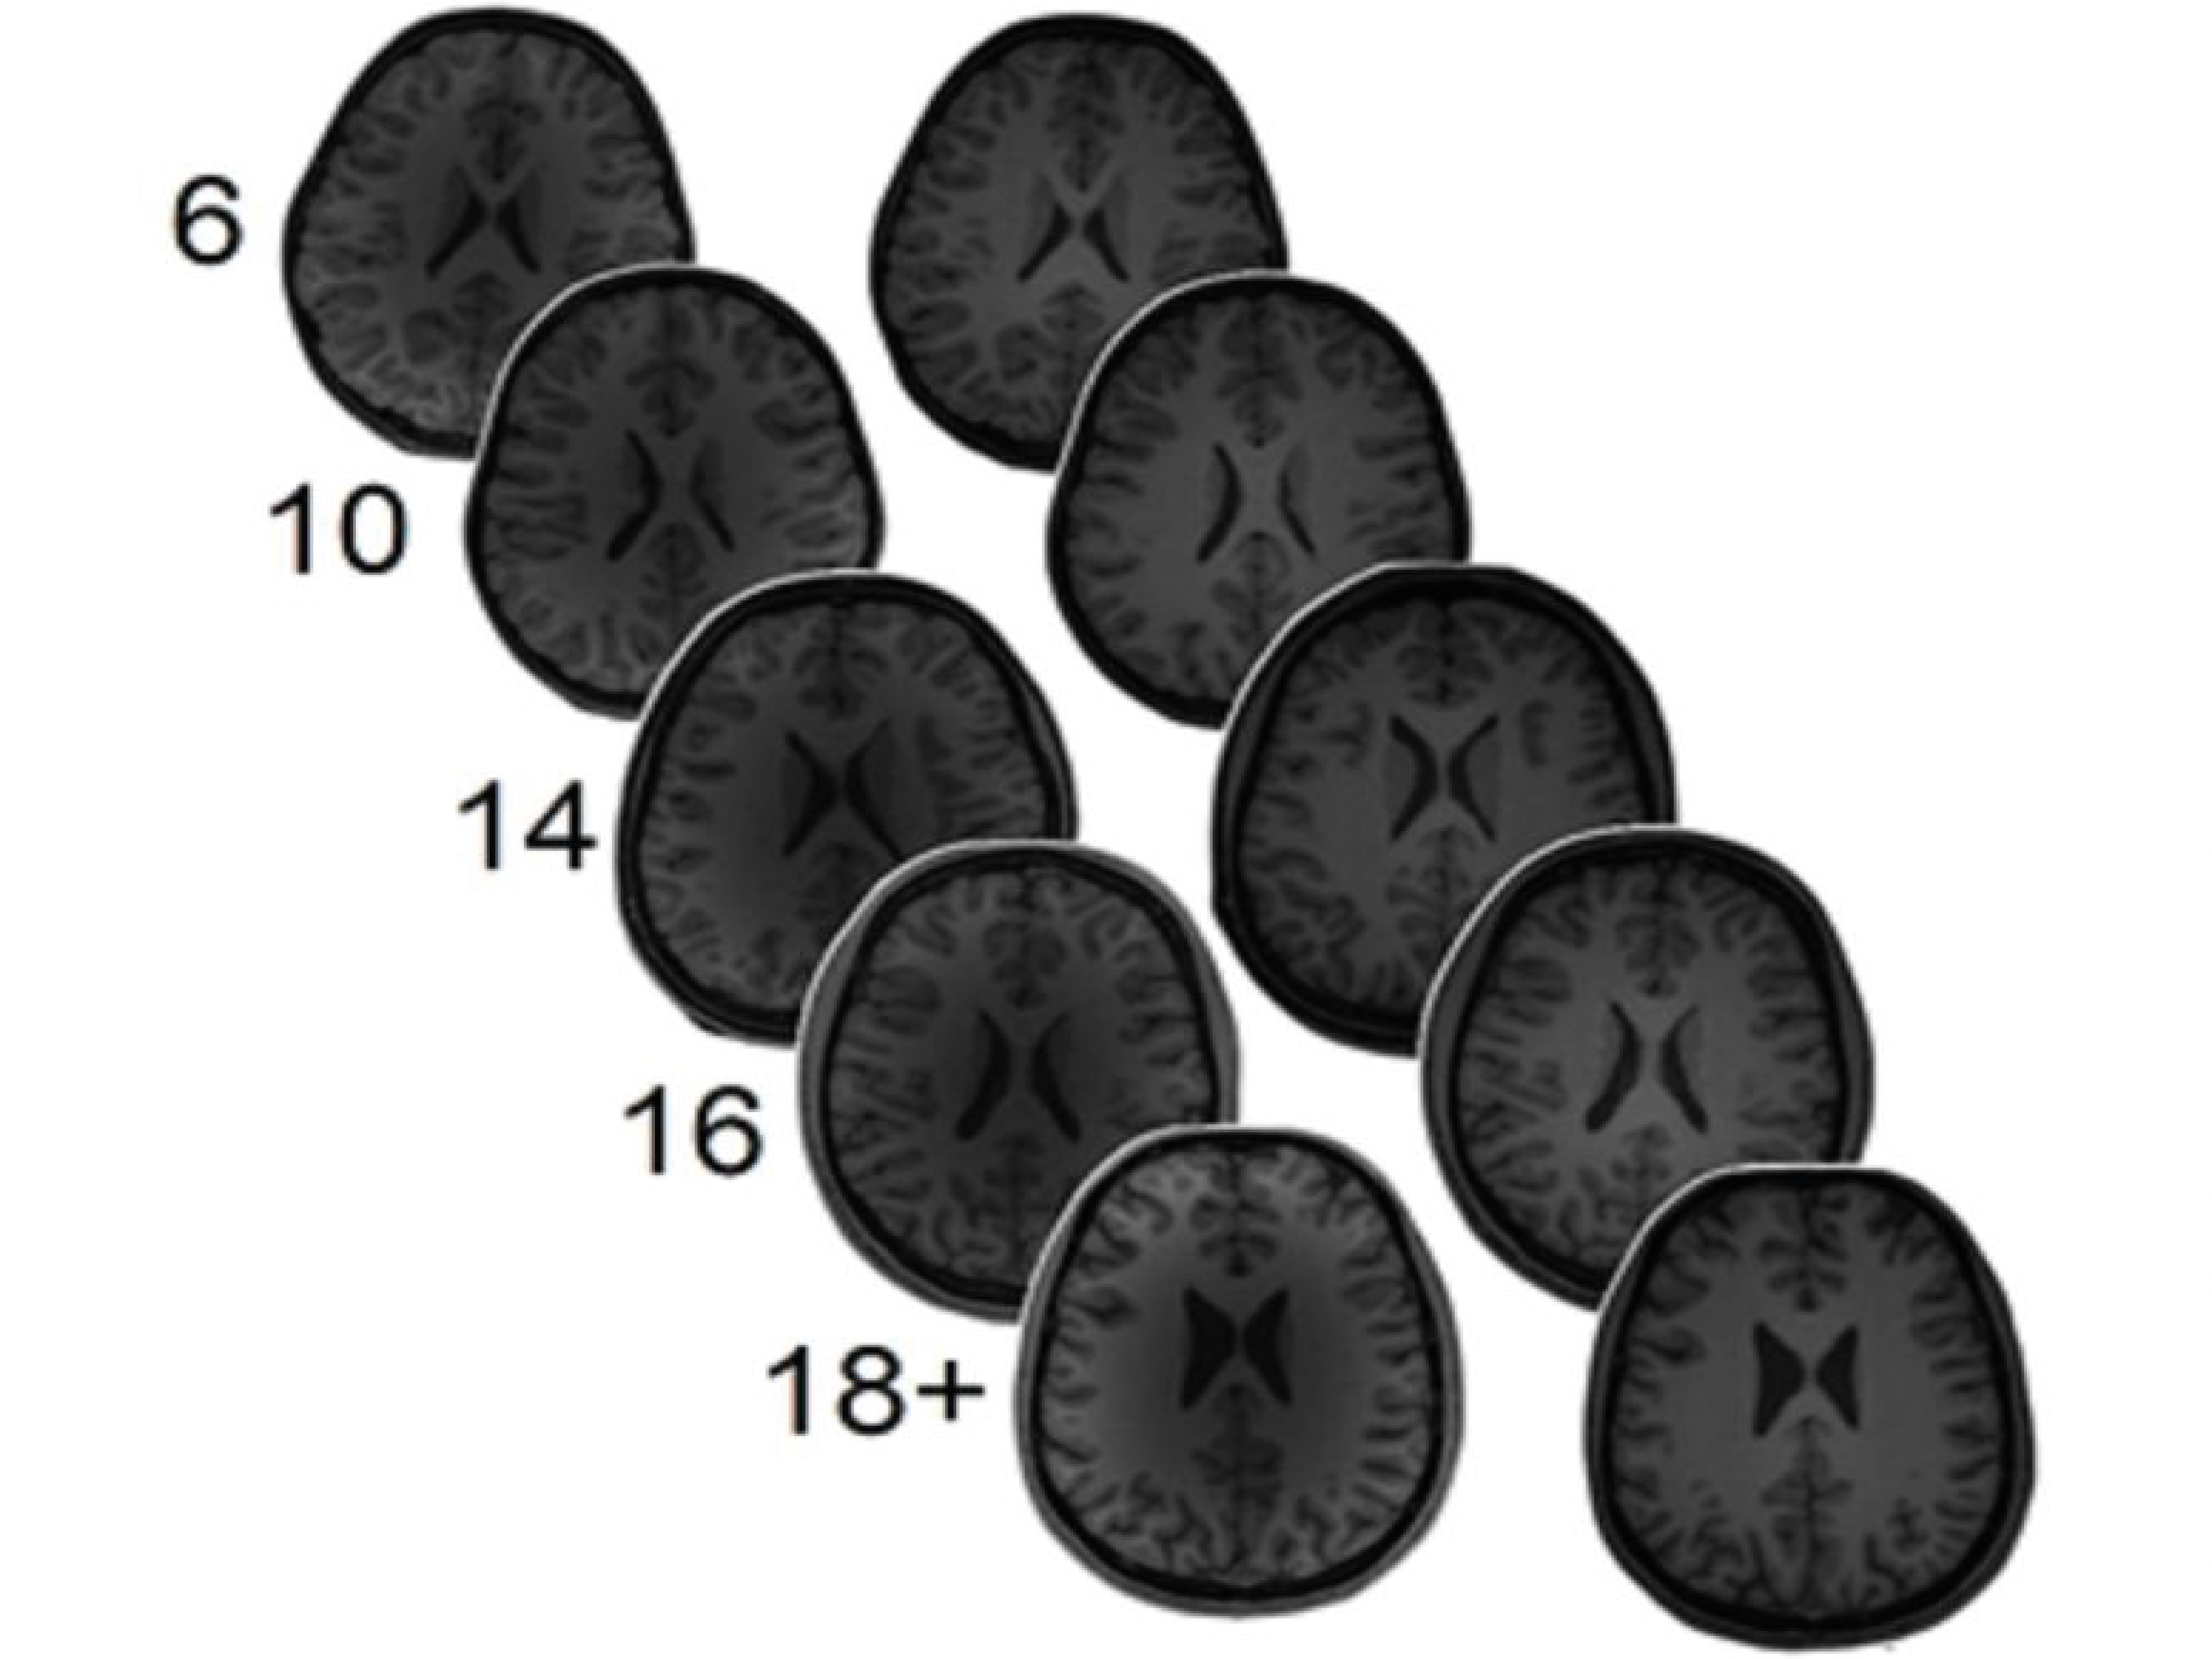

Levels of brain excitement/inhibition are believed to be associated with learning, particularly throughout critical times. However, little is known about their connection to complex learning that can occur over the years. To attend to this concern, the scientists gauged the levels of GABA and glutamate in 255 people, with ages varying from 6-year-olds to university students. The individuals additionally took two mathematics achievement tests, and their performance on the arithmetic problems was associated with the GABA and glutamate degrees.

The group found that amongst the younger faction, greater GABA degrees in the left intraparietal sulcus of the brain (a fold in the top, left, back part of the mind) were connected with better mathematics fluency, and the reverse applied to the glutamate. In adults, the results were nearly contrary; low GABA concentrations were linked with better mathematics fluency, and once more, the reverse held for glutamate. Since the individuals were examined twice, about 1.5 years apart, the scientists were also able to show that natural chemical levels at the time of the very first test could anticipate mathematics accomplishment at a later day.